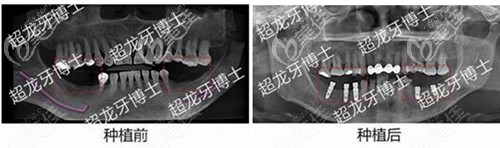

長春超龍牙博士口腔種植牙怎么樣?李平醫(yī)生做單顆種植牙病例可參考 b637 G0 V0

年紀輕輕的就掉了一顆牙,想實現吃嘛嘛香,一番攻略后,推薦長春超龍牙博士口腔種牙,具體長春牙博士口腔種牙怎么樣呢?且聽我慢慢講來!